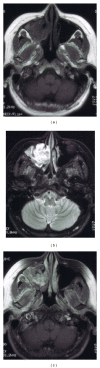

Objective. To study the clinical and pathological characteristics of patients with organized hematoma with malignant features in maxillary sinuses. Subjects and Methods. This was a retrospective study of five patients who were treated surgically for organized hematoma. The preoperative CT and MRI findings were studied clinically. The expressions of CD31, CD34, and periostin in surgical samples were investigated by immunohistochemistry. Results. The clinical features of organized hematoma, such as a mass expanding from the maxillary sinus with bone destruction, resembled those of maxillary carcinoma. However, CT and MRI provided sufficient and useful information to differentiate this condition from malignancy. Surgical resection was the first-line treatment because of the presence of a firm capsule. Characteristic histopathological findings were a mixture of dilated vessels, hemorrhage, fibrin exudation, fibrosis, hyalinization, and neovascularization. The expressions of periostin, CD31, and CD34 were observed in organized hematoma of the maxillary sinus. Conclusion. The expressions of periostin, CD31, and CD34 were observed in organized hematoma of the maxillary sinus. Organized hematoma is characterized pathologically by a mixture of bleeding, dilated vessels, hemorrhage, fibrin exudation, fibrosis, hyalinization, and neovascularization. CT and MRI show heterogeneous findings reflecting a mixture of these pathological entities.